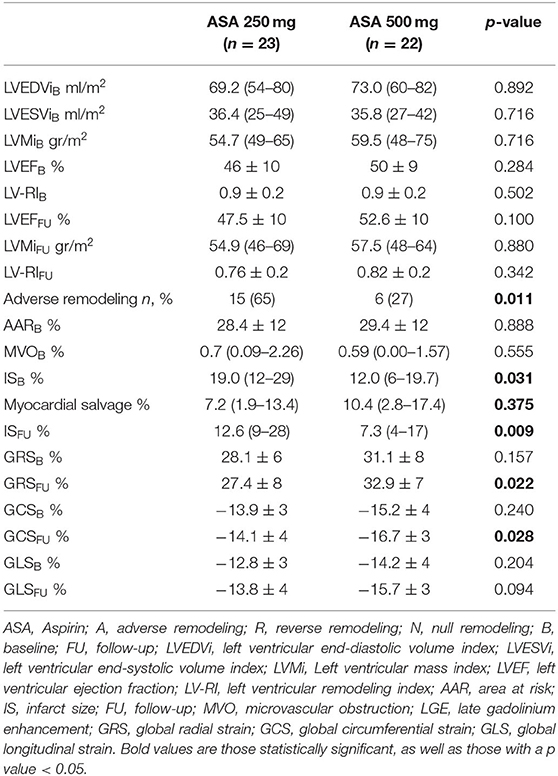

Among cardiovascular drugs administered before PCI, patients with LV adverse remodeling were less frequently treated with ASA loading dose (500 mg), compared to those with reverse or null remodeling (Table 1). Thus, we decided to assess the ASA loading dose effect according to LV remodeling groups. Among the 45 STEMI patients who received a traceable dose of ASA before PCI, 22 STEMI underwent to ASA loading dose, and 23 patients to ASA 250 mg. No differences according to demographic and clinical variables between the two groups were found (Table 3). Patients receiving ASA loading dose before PCI had lower MVO and lower IS extent at baseline and FU-CMR and better strain values (GRS and GCS) compared to those treated with ASA 250 mg (Table 4). Moreover, in the ASA loading group a significant improvement of GCS and GLS, but not GRS values, between baseline and FU-CMR exams (GCS −15.09 ± 3.8 to −16.7 ± 3.2%, p = 0.010, GLS −14.1 ± 3.9 to −15.7 ± 3.2%, p = 0.011, GRS 31.0 ± 7.8 to 32.9 ± 7%, p = 0.104) was noted. Meanwhile, no significant differences of GCS and GLS values between two paired CMR exams within the group treated with lower ASA doses (GCS −13.8 ± 3.5 to −14.1 ± 3.9% p = 0.612, GLS −12.9 ± 3.3 to −13.8 ± 3.7%, p = 0.232, GRS 28.2 ± 6.6 to 27.4 ± 7.9%, p = 0.594) were observed (Figure 4).

Table 3. Demographic, clinical, pharmacological, and angiographic characteristics according to the ASA group.

Protective Effect of 500 mg Aspirin Administration Prior to PCI

Regarding clinical and procedural characteristics, among the LV remodeling groups, a strong difference in pre-pPCI ASA loading dose was found, suggesting its potentially protective role in preventing early adverse remodeling. Besides, a lower IS extent in patients who received a 500 mg dose of ASA at baseline and FU-CMR was found. These findings are in agreement with those reported in elective procedures, where an ASA reload of 325 mg before PCI improved reperfusion indices, reduced myocardial “no reflow” and periprocedural myocardial injury, by blunting post-PCI increase of thromboxane B2 production (28). Moreover, a higher ASA dose before revascularization was also associated with an improvement of LVEF (28). A possible explanation could be due to the effect of high ASA doses in inhibiting post-ischemic LV remodeling process (29), by suppression of proinflammatory cytokines, reduction of collagen deposition, and left ventricular hypertrophy as demonstrated in animal models (30). Indeed, Muller et al. (31) observed a reduction of collagen production and LV hypertrophy in a model of angiotensin II induced organ damage in rats pretreated with 600 mg of aspirin, reporting that high ASA doses decreased mortality, cardiac hypertrophy, fibrosis, and albuminuria independently of blood pressure, by inhibition of IKK/NF-κB pathway. Meanwhile, Adamek et al. (29) demonstrated that high ASA doses, after left coronary artery ligation, suppressed inflammatory response in animal experiments, by inhibiting proinflammatory cytokines such IL-1β and TNF, even though not affecting LV remodeling.

As previously reported, a longer time to reperfusion as well as poor reperfusion indices can determine myocardial injury and LV adverse remodeling (19). In our study, although the greater percentage of thrombo-aspiration might explain the higher rate of adverse remodeling in the lower ASA dose group, an ASA loading dose of 500 mg remained, at multivariate analysis, a significant protective factor independently from IS.

Furthermore, for the first time, ASA's role in improving myocardial contractility at FU-CMR has been examined. As FT-CMR has been demonstrated to be a valid and accurate tool to assess short and long term efficacy of cardioprotective drugs such as metoprolol (13, 32), no data about the effect of ASA on early LV remodeling and myocardial strain have been reported previously. Indeed, few clinical studies investigated the optimal ASA dose before pPCI in STEMI patients (16), which remains to be defined. In a retrospective study by Berger et al., the higher ASA dose in STEMI patients was associated with a greater risk of moderate-to-severe bleeding than lower doses, but there was no difference in 30 day mortality or ischemic related outcomes (33). The CURRENT-OASIS 7 trial compared open-label high-dose (300–325 mg daily) to low-dose (75–100 mg) aspirin in patients with acute coronary syndromes undergoing planned PCI (34). In a recent retrospective study by Rossi et al. (35), a high intravenous ASA dose in STEMI patients increased in-hospital mortality if compared to patients treated with intravenous low doses or oral doses, but it did not influence cardiovascular events after 1-year follow up. Recently, a clinical randomized trial demonstrated that an intravenous ASA dose of 250–500 mg compared to 300 mg orally can lead to complete inhibition of thromboxane generation and platelet aggregation, indicating the efficacy of higher doses in ameliorating myocardial reperfusion (36). The effect of higher ASA doses in ameliorating IS and contractility and in preventing LV adverse remodeling in our study may be interpreted by a complete inhibition of platelet cicloxigenase 1 activity (COX1) (28). Indeed, as demonstrated in the REMODELING prospective cohort trial in STEMI patients treated with antiplatelet agents, increased levels of platelet activation and inflammation may be responsible for post-STEMI LV adverse remodeling processes (37). High platelet reactivity is frequent after STEMI and is associated with major adverse cardiovascular and cerebral events, especially if associated with P2Y12 inhibitors platelet activity (38). Moreover, plasma thromboxane B2 has been reported to have a role in modulating myocardial reperfusion and has been hypothesized to have a vasoconstriction effect, modulated by COX-1 (39).